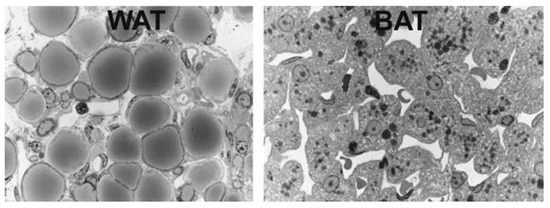

BAT can be visualized using 18F-fluorodeoxyglucose (FDG), an intravenously administered radioactive glucose analog, which is taken up but not metabolized (originally used to delineate metastatic cancers) and viewed using positron emission tomography (PET) scans (

Light microscopy of murine white adipose tissue (WAT), left, and brown adipose tissue (BAT), right. White adipocytes are roundish with unilocular lipid droplets. Brown adipocytes are polyhedral with multilocular lipid droplets and a centrally positioned nucleus. From: [9] (reproduced with permission).

The third paradigm shift featured the increasing significance of BAT in both health and disease status. Of note, BAT, with its characteristic small multilocular adipocytes and central nuclei (as opposed to larger unilocular white adipocytes with nuclei at their peripheral rims), as well as granular cytoplasmic appearance on haematoxylin and eosin (H&E) staining, was demonstrated as a component of epicardial AT (EAT) surrounding coronary arteries. Uncoupling protein-1 (UCP-1) is unique to BAT as it uncouples mitochondrial oxidative phosphorylation, thus producing heat instead of ATP by non-shivering thermogenesis, and mRNA